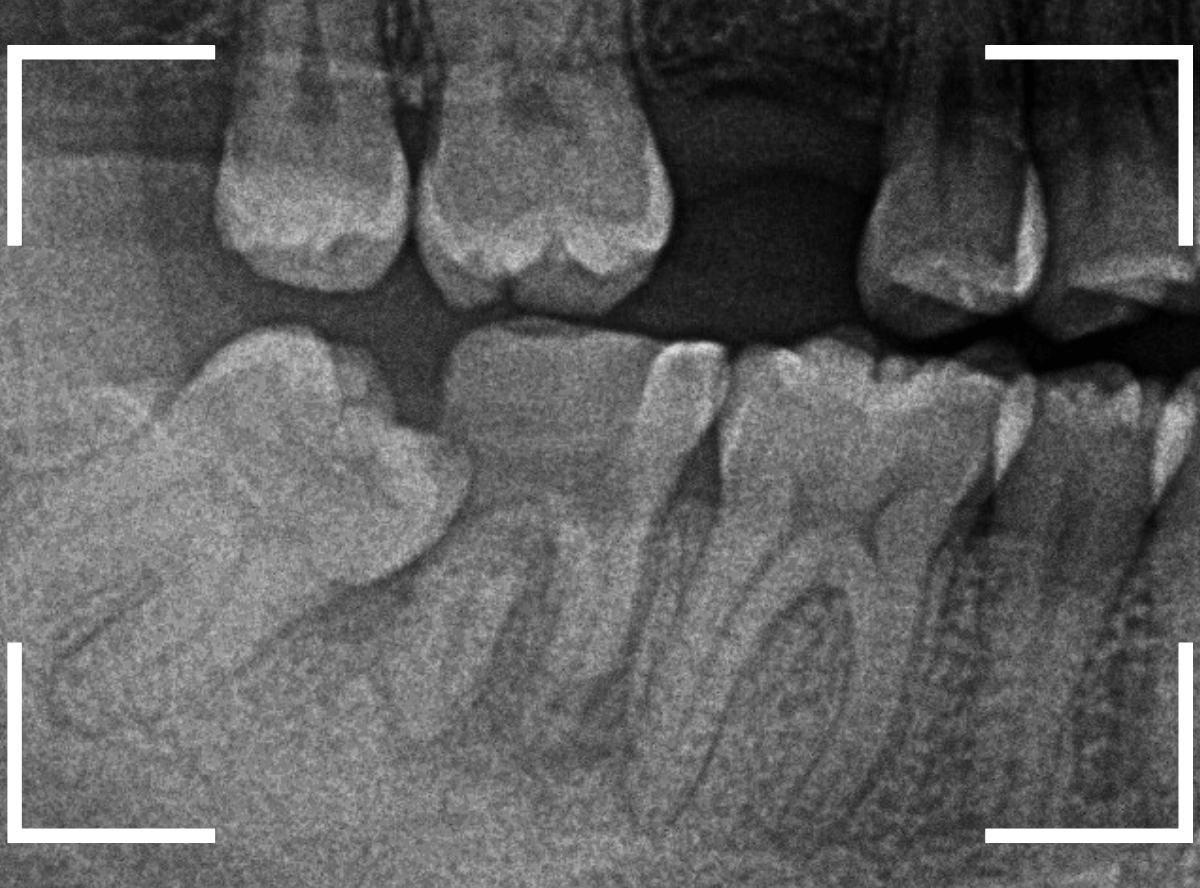

レントゲン写真で確認します。

青い線が歯の形と神経です。

赤い線が、虫歯です。

初見でも想像がつきましたが、かなり虫歯がひどく、治療して再び噛む事が出来るようにするのが不可能で、抜歯をする事になりました。

一つ手前の歯も大きな虫歯で根元までボロボロです。

これではどちらが痛みの原因になってもおかしくありません。

へし折れてしまっている根もありますが、わりとはっきり根の状態がレントゲンに写ってますので、抜きやすい状態かもしれません。

しかし、レントゲン写真で確認すると、実際には虫歯でボロボロで、歯の根っこだけの状態なのがわかります。

残念ながら抜歯が必要ですが、抜歯も難しくなる可能性が高いケースです。

レントゲン写真でも、ほとんど残ってる歯が確認できません(残根状態(歯の根っこだけ残っている状態)といいます)。

これでは、抜くのも大変そうです(><)